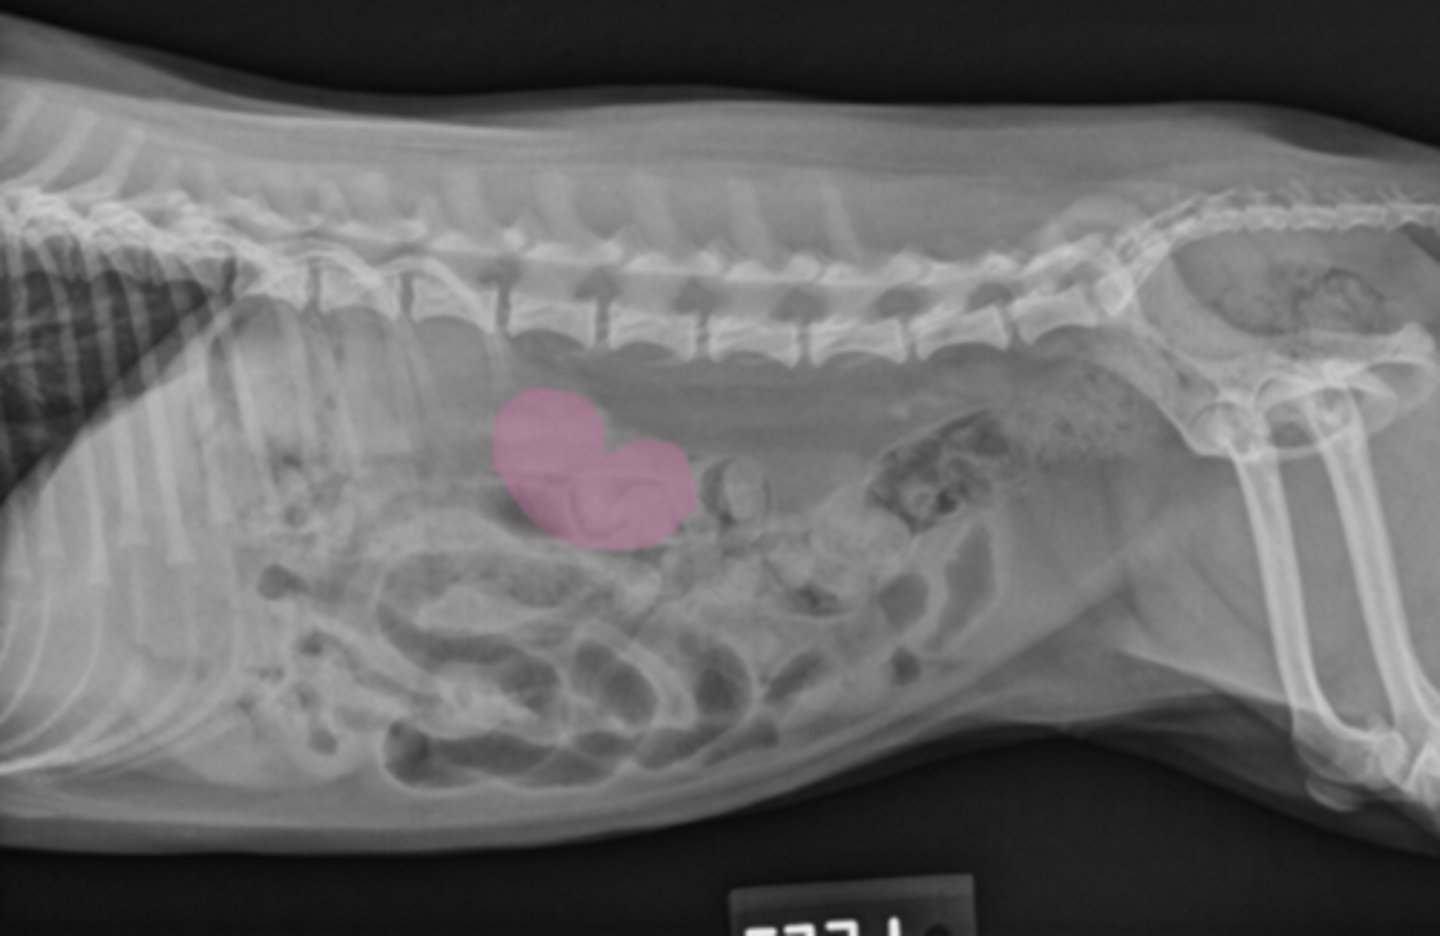

GDV

10 yo lab with abdominal distention, panting- what has caused this?